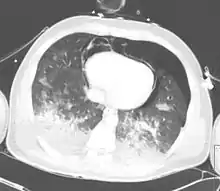

| CT scan showing pneumopericardium with pneumomediastinum, pneumothorax, hemothorax, and pulmonary contusion after severe chest trauma[1] | |